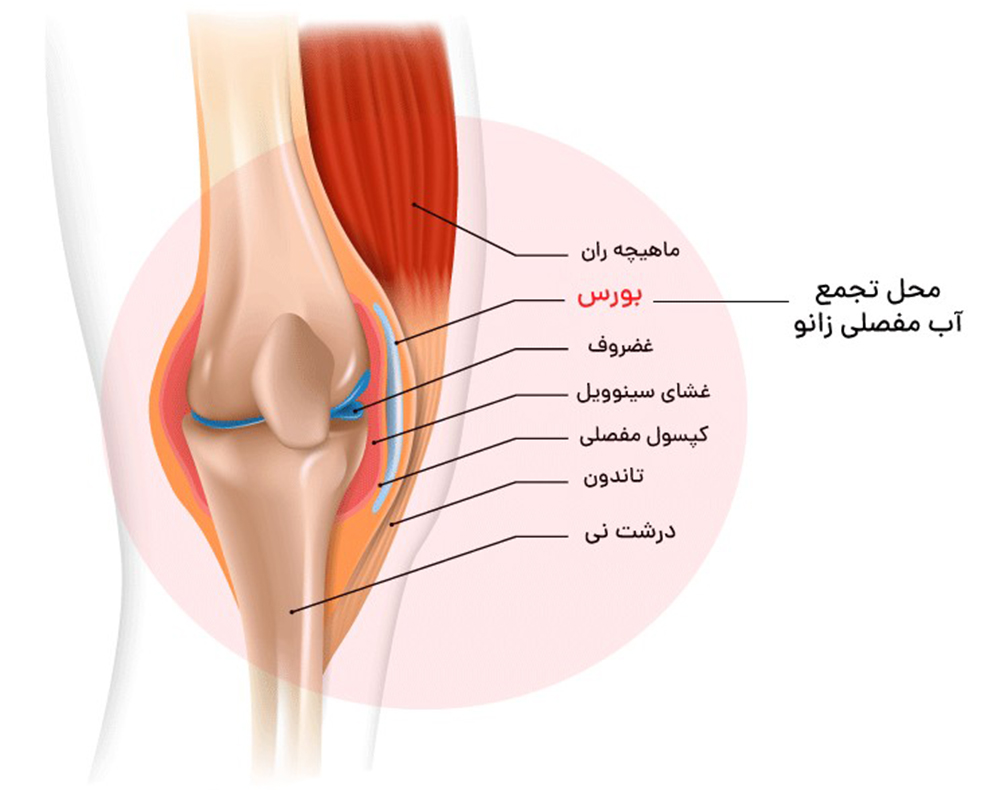

به عنوان مثال، مفصل زانو دارای چهار رباط اصلی است، یکی در هر طرف زانو و دو رباط که به صورت مورب در جلو و پشت کاسه زانو قرار دارند. این رباط ها به تثبیت زانو کمک می کنند و از حرکت بیش از حد به سمت چپ یا راست، جلو یا عقب جلوگیری می کنند.